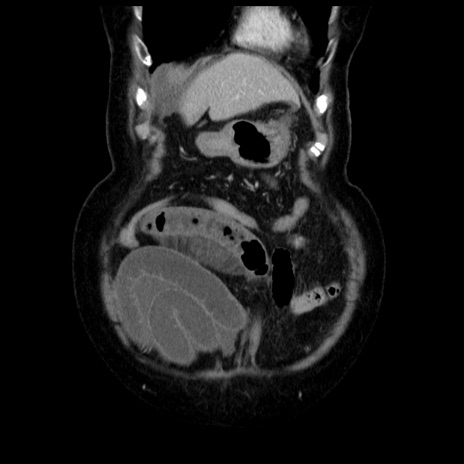

横断像